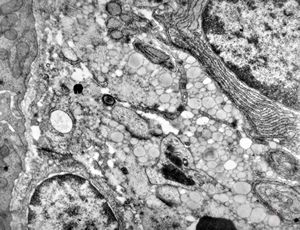

jejunum … lipid malabsorption

duodenum … lipid malabsorption